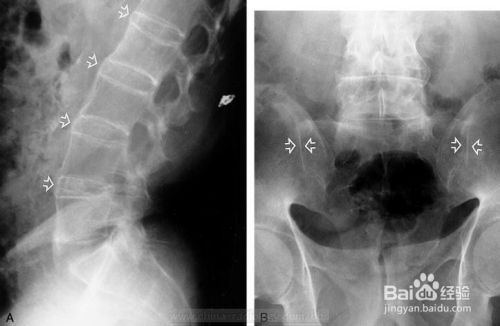

三、患者的腰痛和腰骶部僵硬感反复发作,腰痛和两侧臀部疼痛间歇或交替发生,按压骶髂关节会出现疼痛,X线检查结构改变,患者早期发现病情很重要.